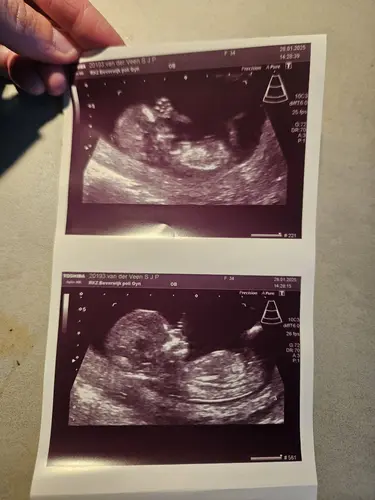

13+1 🩷💙? Ik denk zelf een meisje

Ja meisje 🩷🩷🩷